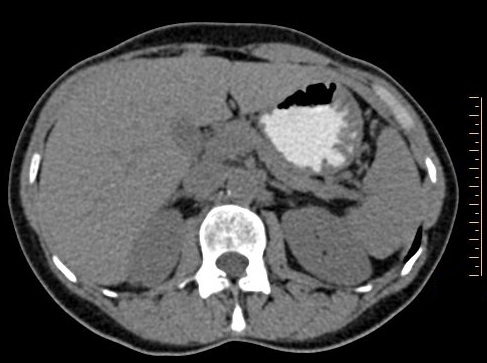

. Image radiologique TDM en

coupe axiale a travers le pancreas avec de contrast

baryte gastrique . Normalemant le pancreas

avait une densite egale les muscles paravertebrales .

Sa bord est lisse , et regulier , se situe

entre vertebre dorsal D12 a vertebre lombaire L3 |

Par l'age ou par le degre de l'infiltration

graisseuse , le pancreas avait une densite en

croisant

eleve , sa bord devient lobulee ,

epaissisement , moins lisse et irregulier . Image au

dessus est

TDM en coupe axiale a trasvers le pancreas

|